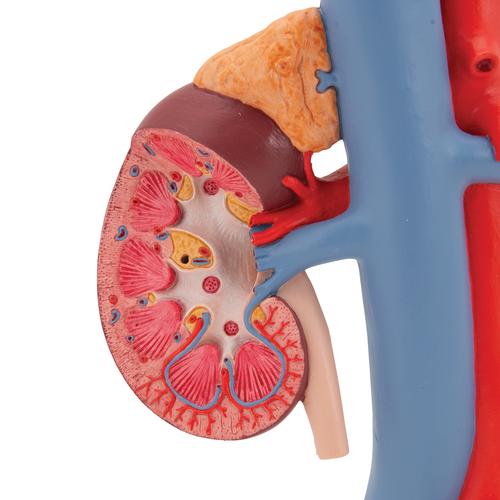

Эта модель в натуральную величину демонстрирует почки с надпочечниками, мочеточники, внутрипочечные сосуды и крупные кровеносные сосуды, расположенные в непосредственной близости от почек. Съемная передняя половина правой почки позволяет увидеть почечную лоханку, чашечки, корковый и мозговой слои почки. На подставке.